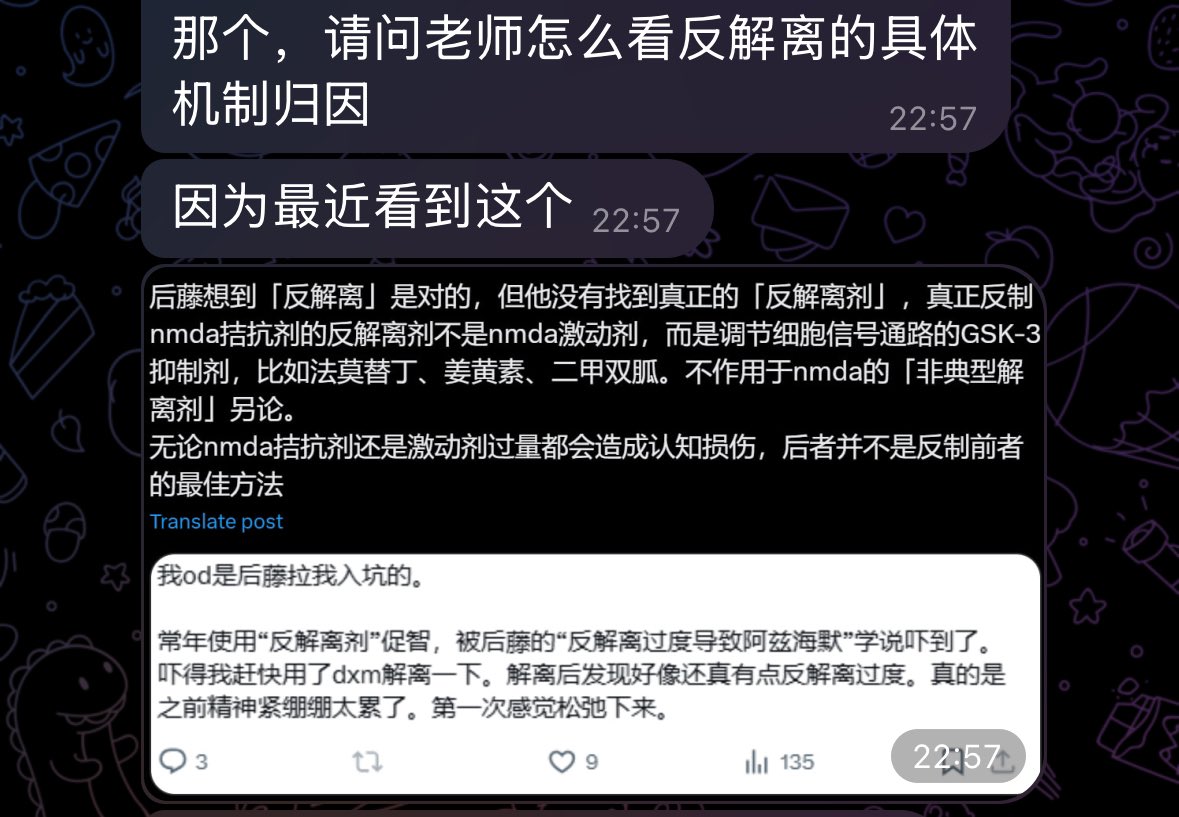

关于后藤提到过的“反解离”

首先,从定义上讲,“反解离(anti-dissociative)”并不是一个标准的医学术语或者广泛认同的药理学分类。在正规资料,比如医学文献、维基百科、精神药理学教科书中,目前并没有“反解离药物”这个正式概念。

看上去像是为了描述某类特定效应而创造的术语(可能是nmda受体活性增强),用来对抗因NMDA受体拮抗剂(比如氯胺酮、DXM、PCP等)引发的解离体验(dissociation)。

那么更常见的是将其归入认知增强剂(cognitive enhancers),特别是改善认知连接性(connectivity)和现实感知(reality testing)的类型。

但其实在药理学上,单纯用“受体激动剂”来逆转“受体拮抗剂”的效应,有时会导致过度激活。

对于NMDA受体而言,过强的NMDA活化本身就与兴奋性毒性(excitotoxicity)和精神病样症状(psychotomimetic effects)有关,比如谷氨酸风暴可以引发严重的焦虑、妄想、乃至癫痫。

也就是说,简单地“激动-解除拮抗”在中枢神经系统是很危险的做法,尤其是对于易感个体(如有精神分裂素质的人)。

科学的处理方式一般是通过更细致的调节,比如微调NMDA/AMPA平衡、调节其他辅助途径(如GABA、5-HT、mGluR受体),而不是简单粗暴地用“NMDA增强剂”去顶回去。

而临床处理药物中毒中,其实医生更常用的做法是保守、支持性的治疗,比如补液,促进代谢,必要时镇静,以及监测生命体征防治并发症。

药物拮抗与受体激动之间,往往牵扯到的是复杂的适应性变化(receptor upregulation/downregulation),

不是简单的“给多一点刺激就能抵消”的关系